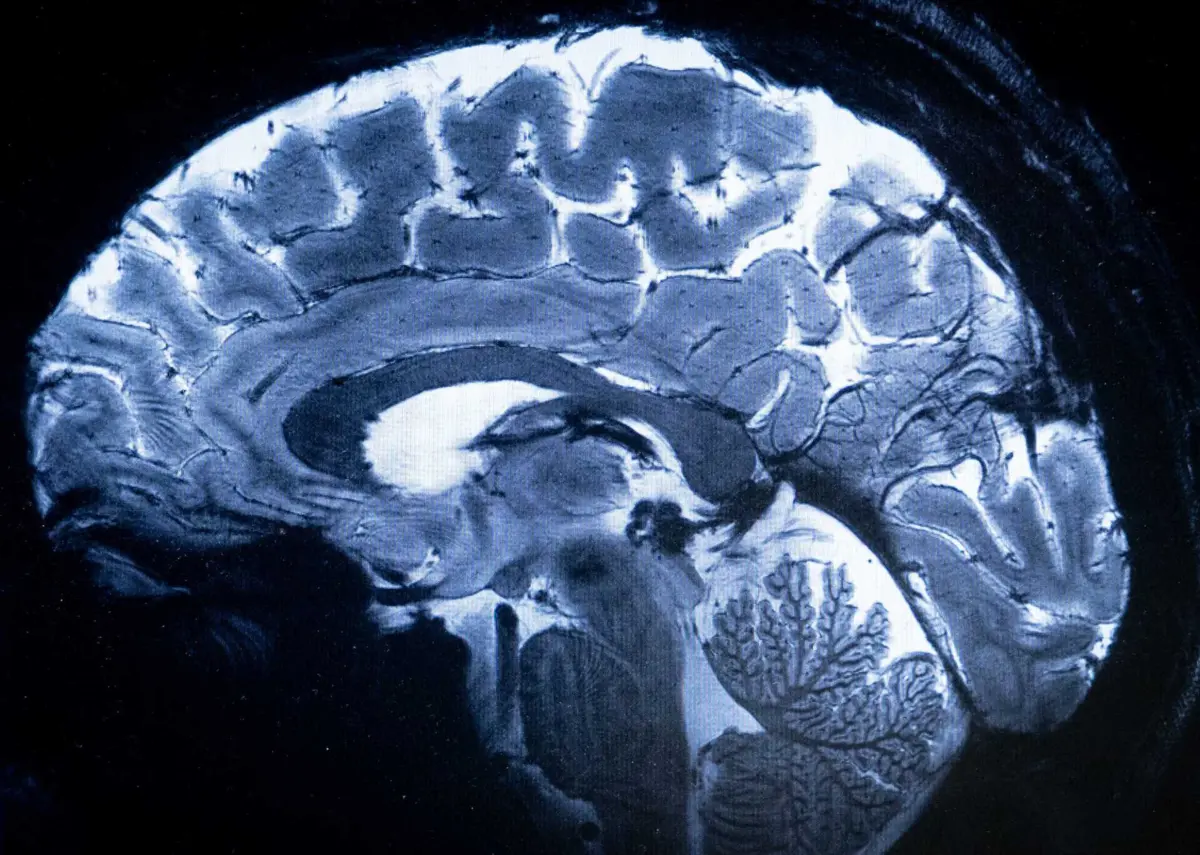

A investigação, realizada por cientistas da Universidade de Amesterdão, pretendia replicar um estudo publicado em 2011 e baseado em 90 universitários do Reino Unido, cujas imagens cerebrais mostravam que os votantes progressistas e conservadores apresentam diferenças nos seus cérebros.

Agora, a equipa quis comprovar os resultados com um grupo de participantes maior e mais diversificado e, para isso, analisou os ‘scanners’ cerebrais por ressonância magnética de 928 indivíduos, com idades entre 19 e 26 anos, com níveis de educação e identidades políticas representativos da população holandesa.

As ressonâncias magnéticas utilizadas no estudo apenas proporcionaram informação sobre a anatomia das distintas regiões cerebrais, mas os investigadores acreditam que trabalhos futuros devam integrar informação sobre as conexões funcionais entre a amígdala e diferentes partes do cérebro.